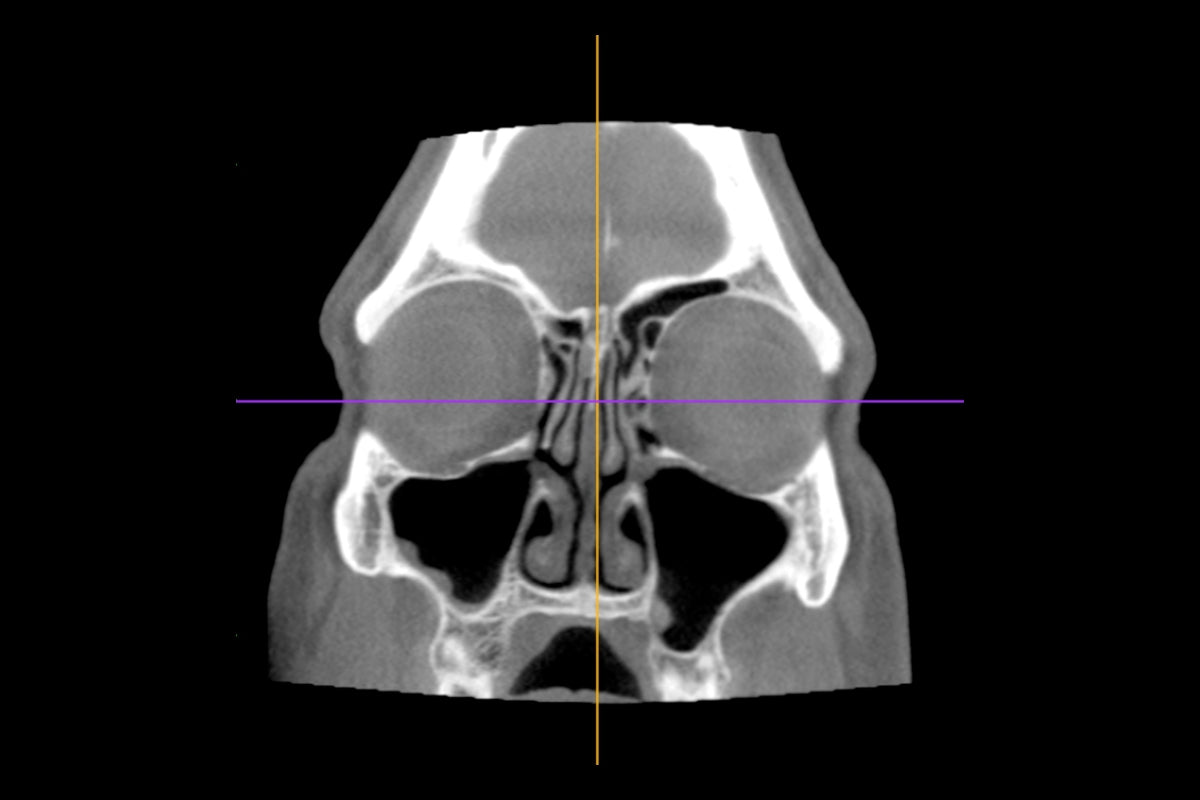

Model of airflow through the nasal passages

NIDCD grantee Kai Zhao, Ph.D., Ohio State University (NIDCD grant RO1DC013626), and Ohio State University Wexner Medical Center Media and Public Relations

The shape and size of your nasal cavity play a big role in how allergies affect you. When the nasal passages are shaped a certain way, it can change how air flows and how allergens, like pollen, settle in your nose.

We then used all of this rich data to develop a machine-learning model trained on a combination of CT scans, facial recognition landmarks, symptom reports, and geo-tagged pollen data. This model helps us explore the relationship between nasal anatomy and allergy symptoms. Our findings suggest that certain nasal structures are more prone to trapping pollen, leading to more severe congestion and other allergy symptoms.